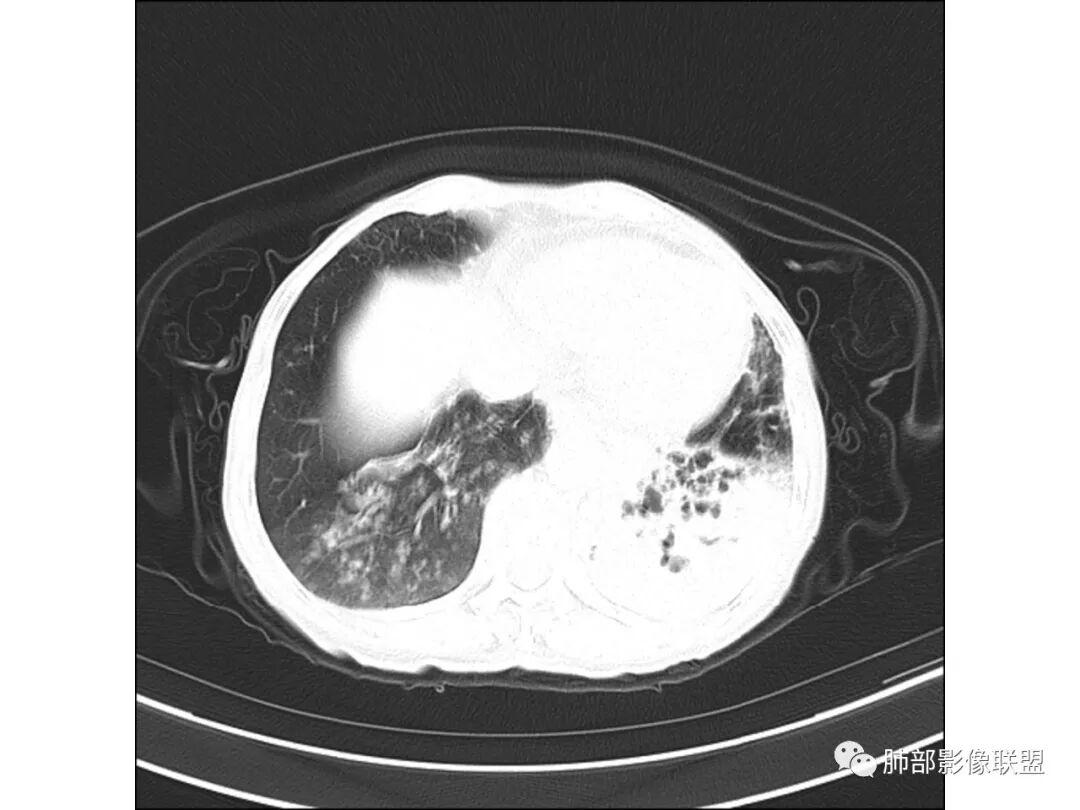

慢性迁延不愈患者 发热伴脓痰 双肺多发小结节伴磨玻璃影 左肺下叶体积缩小 支气管扩张伴实变 实变内支气管不规则 平扫密度尚均较肌肉稍低 支气管扩张感染基础上合并淋巴瘤待查 建议增强穿刺

老年女性,慢性病程,有反复咯血、发热,左下胸廓塌陷,双肺下叶多发片状实变影,伴多发结节,左下肺实变为主伴卫星灶,支气管扩张,伴虫噬样空洞及支气管壁钙化,首先考虑结核,鉴别粘液腺癌

老年丶反复发作2年,但双肺下叶多发腺泡结节,延气道分布,影像不符合陈旧病变,左下实变影,伴牵拉支扩,考虑慢性病变首先考虑吸入性肺炎,建议结合病史是否有隐性误吸,可查胃镜、气管镜丶钡透,除外食管、气管瘘。鉴别腺癌丶放线菌丶努卡菌丶NTM

患者老年女性,反复咳嗽 咳痰 活动后胸闷 气短,胸ct:病变以左肺下叶体积缩小,呈大片实变,实变组织内可见 左肺下叶支气管开口扩张,右肺下叶背段多发结节样病灶,周围有毛玻璃影。良性考虑感染性病变,ABPA ?结核?;恶性考虑:粘膜相关淋巴瘤。

双肺多叶段多发腺泡结节,延气道分布,双下肺为诸,左下肺大片实变影,伴牵拉支扩,老年人首先考虑支气管肺炎。鉴别腺癌。

双下肺多发腺泡结节,左肺下叶实变,彭隆,结核伴感染,鉴别结核伴粘液腺癌。

双肺下叶多发片,结节,左下肺实变,局部膨隆,粘液腺癌?鉴别结核。

晨读病例,老年女性,病程长,左侧胸廓缩小,双下肺叶多发片状实变影,伴多发结节及树芽征,左下肺实变,有坏死空洞,支气管扩张壁增厚有钙化,考虑结核,鉴别粘液腺癌,淋巴瘤,排除异物

病灶位于中下肺部,左下叶应该是源头,其余是播散灶

大家看看这支气管

这些支气管扩张

这些应该是胸水

支气管扩张、扭曲成团,附近钙化灶

这例左下叶的体积是整体缩小的,左下叶的支气管主干稍微小一点点,然后左上叶的下舌段也有类似的病灶,然后我们看到一团乱的支气管扩张,但它有特点,边缘凹凸不平。那什么样的支气管扩张边缘会如此凹凸不平呢,等我截个图:

首先这幅图支气管很多地方是扭曲的,远端扩张的特别厉害。如果是肿瘤,首先考虑淋巴瘤,因为支气管可直达远端,稍扩张,但是它的前提是周围要实性占位的,而且它不会这样扭曲变形。我们看这个病例的支气管扩张,它支气管扩张占大部分区域,中间稍有些实性的结构,这就不符合了。这幅图你会发现所有支气管都是扩张的,实性部分偏少,外围胸水。所以我更倾向慢性炎性病变,能够引起支气管扩张的炎性病变有哪些?结核?NTM?支扩伴感染?大方向是慢性炎性病变。这些左下肺播散出来的病灶,咳中等量黄浓痰,我考虑还可能合并细菌感染。

1.双肺斑片影、大小不等结节影,边界不清,密度较均一,钙化不多见,可见树丫。

2.左肺下叶大范围病灶,其间柱状支气管扩张相当显眼。

这些都支持慢性炎性改变。